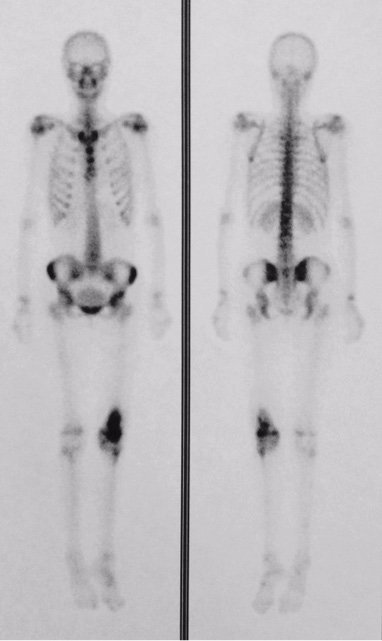

ABA, female, 16 years old, presented pre-existing bilateral hearing loss of unknown etiology, and asthma. The patient was admitted for examination due to a pain in her left thigh. Facing the need to rule out a neoplasia diagnosis, a bone scintigraphy was requested, which evidenced a focal area of increased uptake in the distal metadiaphyseal area of the left femur, with a highly aggressive osteoblastic lesion (Figure 1). A bone biopsy was performed, and its result evidenced medullary fibrosis, chronic inflammation with multinucleated of giant cells and areas fusocellular proliferation, compatible with chronic osteomyelitis. Cultivations of matter, serological investigation, autoantibodies and metabolic alterations were negative. In face of the clinical picture, the CNO diagnosis was performed, and treatment was initiated with pamidronate and prednisone, with partial improvement. Bisphosphonate was administered for 22 months (withdrawn due to treatment failure), and then, methotrexate was administered for 6 months, when it was suspended due to urticarial reaction. In January 2016, the patient presented a new pain episode, this time, in the right distal thigh and knee, which raised a suspicion of an additional focus of osteomyelitis during disease activity, which was confirmed by a new scintigraphy. In accordance with the reviewed literature and bearing in mind a refractory case to the usual therapy, it was decided to administer an anti-TNFα (infliximab), at a dose of 200mg per infusion (3.5 mg / kg), with applications every 8 weeks, with important clinical improvement in 4 months of evaluation until this moment, with recovery from the pain, besides standardization of inflammatory activity tests and new scintigraphic improvement. It is important to highlight that during the applications the patient did not present any side effects to the medication use, nor did she present infectious pictures in the period.

CNO is a rare inflammatory bone disease with intermittent course [8], characterized by recurring multifocal bone lesions [9]. The literature describes a female 5:1 predominance [5]. The most commonly affected age group is 8-12 years old, with peak incidence at 10 years old [9]. The diagnosis of CNO is made by process of elimination and is based on clinical, laboratorial, radiological, bacteriological and histological data [1]. Evidence of inflammatory activity is heightened during phases of disease activity, with normalization in periods of clinic remission [8]. Bone biopsy shows nonspecific inflammation, fibrotic or hyperostotic regeneration, and cultures are negative [10]. The scintigraphy reveals increased uptake in the affected areas, and helps perform diagnosis, which is done by process of elimination [8]. There are descriptions of association with other inflammatory diseases, such as Crhon’s disease, palmoplantar pustulosis, psoriasis, Sweet’s syndrome, among others [9]. Nonsteroidal anti-inflammatory and bisphosphonate drugs are recommended as initial treatment [1,3,7,10]. Bisphosphonates appear to be beneficial in reducing the expansion of the bone lesion due to the antiosteoclastic activity and its anti-inflammatory effect, which can contribute to pain control [9]. Disease-modifying drugs, steroids and anti-TNFα have been used in severe and recurring cases [1,3,7,10,11,12]. Despite reports of a variable response to the use of anti-TNF [11,12], in this case the clinical and laboratory response had been sustained to date, with about 4 months of use of the biological medication, corroborating the reports of clinical and image improvement with the use of anti-TNF.